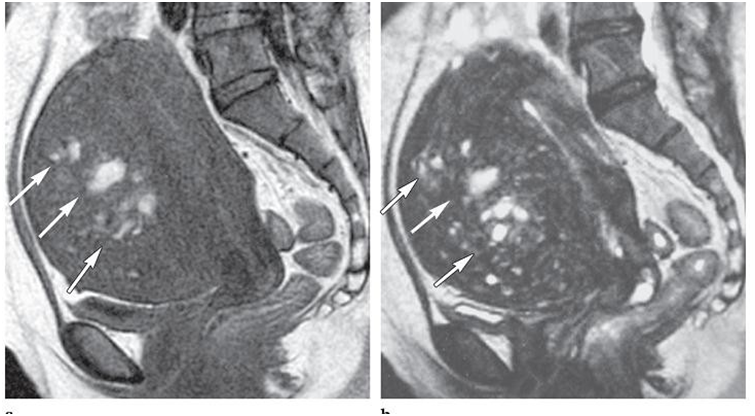

Nang lạc nội mạc buồng trứng

Hình 2. Nang lạc nội mạc buồng trứng (P)

Riêng đối với endometrima, chuỗi xung T1W xóa mỡ đã làm tăng giá trị của CHT trong phân biệt giữa nang LNMTC ở buồng trứng với những u buồng trứng có chứa mỡ như u quái. Hình ảnh CHT của nang LNMTC là hiện diện một hay nhiều khối trong buồng trứng với tín hiệu cao trên T1W và T1 xóa mỡ. Trên T2W có tín hiệu thay đổi từ thấp (còn gọi là shading) đến trung bình hoặc tín hiệu cao, điều này là kết quả của nồng độ protein và sắt cao bởi xuất huyết nhiều lần trong nang LNMTC. Thuốc tương phản không giúp ích nhiều cho chẩn đoán nhưng có thể hữu ích trong những trường hợp nghi ngờ chuyển dạng ác tính.